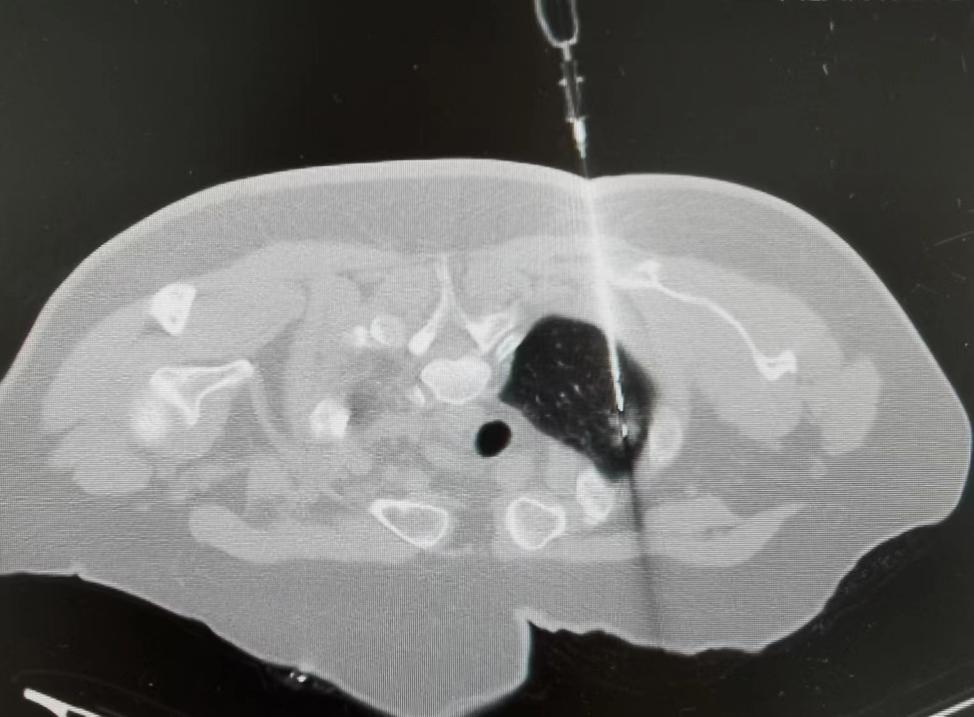

入住肿瘤科后,医护共同对阿姨进行了详细的心理状态评估及检查,在治疗心理疾病的同时,详细对比近几年曹阿姨CT检查变化,考虑右肺上叶尖段磨玻璃结节恶性程度较大,为进一步明确诊断,刘小军医生为其进行了CT引导下经皮右肺上叶尖段磨玻璃结节穿刺活检术,术后病理诊断:原位腺癌。

自2016年以来,肿瘤科已经成功为多例病灶小于1cm肺结节患者通过穿刺活检明确了诊断,为肺癌患者的早诊早治带来了福音。